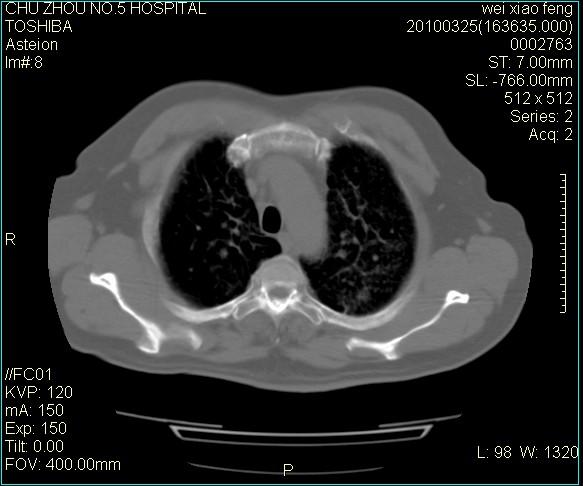

男,60岁,反复咳、痰、喘3月,加重3天。

双肺间质性改变。

考虑双肺血型潘散肺结核/

间质性肺炎伴间质纤维化!不排除伴有职业病!

急性血型潘散肺结核。

双肺间质纤维化,双肺血型潘散肺结核。

考虑间质性肺炎伴间质纤维化。

右肺中叶结节影为原发灶,考虑右肺中叶周围型肺癌并淋巴道转移